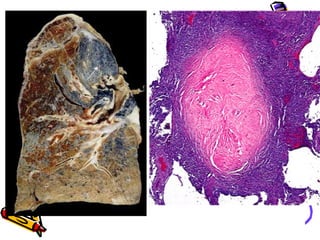

Gross Morphology

• Discrete pale to black nodules <1cm

dia.

• Upper zone of lungs

• Hard collagenous scars-central

softening

• Fibrosis in hilar lymph nodes and

pleura

• Enlarged fibrotic LN with peripheral

(eggshell) calcification

• PMF nodules >2 cm dia+ silicosis

Microscopy

• Concentric hyalinized collagen

surrounded by condensed

collagen,fibroblasts & lymphocytes.

• Birefringent silica particles

(polarized light)

• Nodules incorporate normal lung

tissue into themselves.